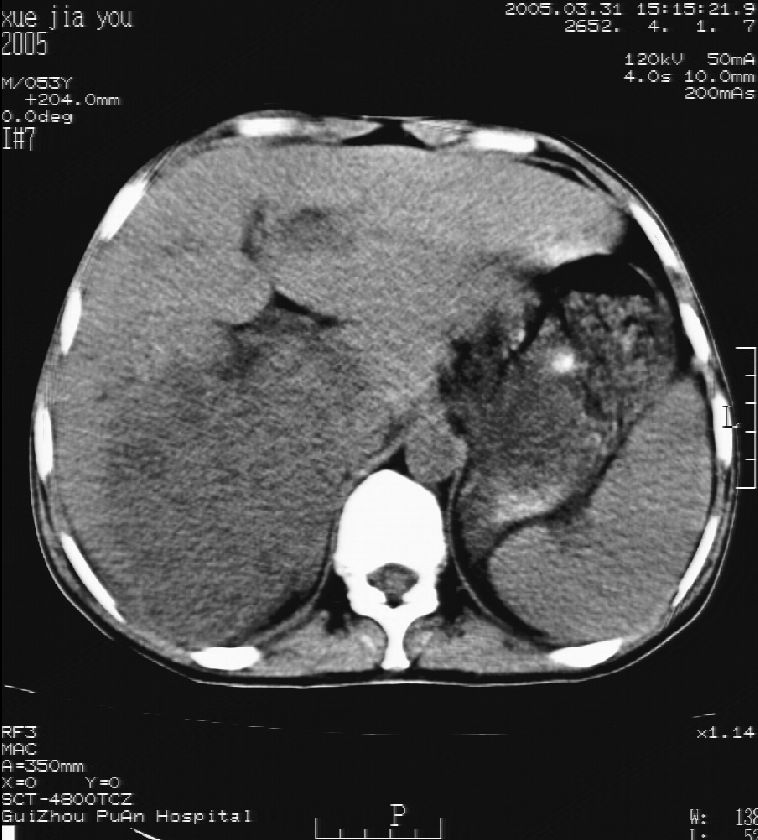

男 55岁  反复上腹痛1年,伴恶心呕吐。2005年做第一次检查后,到外院做b超检查提示肝囊肿,未做任何手术。2006年做过胆总管结石术。骨窗未见异常

这个病灶很有意思,怎么可能没有了呢?我考虑当时很可能是肝脏脓肿(b超示囊肿是有可能误诊的,因为影像表现都是低回声吗?),现在脓肿吸收了,肝脏萎缩,肝裂增宽了.别的肝叶代偿增大,不过现在左内叶的确有个占位,肝内多发结石,脾脏比以前大,不排除有肝硬化可能.建议增强扫描给于定性!!!!

肝胆胰脾平扫加增强

表现:肝左叶前缘见两个大小约2。6*2.6及3.1*3.6cm类圆形稍等密度结节影,ct值约为53hu,边界尚清;其密度不均匀;增强扫描动脉期结节灶强化较周边肝脏明显,静脉期及延迟期内侧病灶强化等同于周围肝,外侧病灶强化稍低于周围肝。余肝实质内未见异常密度影。脾脏未见增大,密度均匀。胆囊未见异常。胰腺未见异常。未见腹水征。

afp为2.1。

考虑肝内胆管多发结石引起的肝内局部炎症,这样可以解释2005年肝右叶病灶的吸收和左叶新病灶.